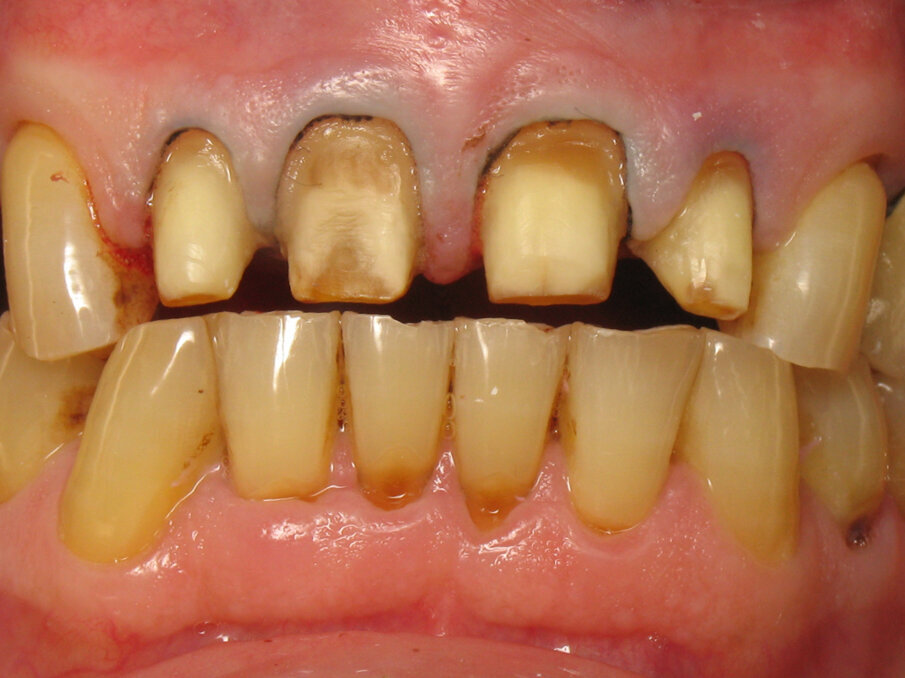

Fig. 11: Initial situation.

Fig. 12: Close-up of the initial situation.

Captured at the same time as Figure 10, Figures 11 and 12 show the initial situation of this patient, who came for a consultation to rehabilitate his maxillary incisors. The diagnosis revealed nocturnal bruxism as the origin of several areas of crown destruction: wear of the incisal edge, abfraction, missing restorations, cracks and a complex coronary fracture. It is easy to understand why the choice of material was zirconia. It is also easy to understand the motivations of this patient to recover his lost smile. This degradation over time is inevitable, but in this patient, it was particularly fast and aggressive. Reversing the course of time was therefore obvious in restoring the dental health of this patient.